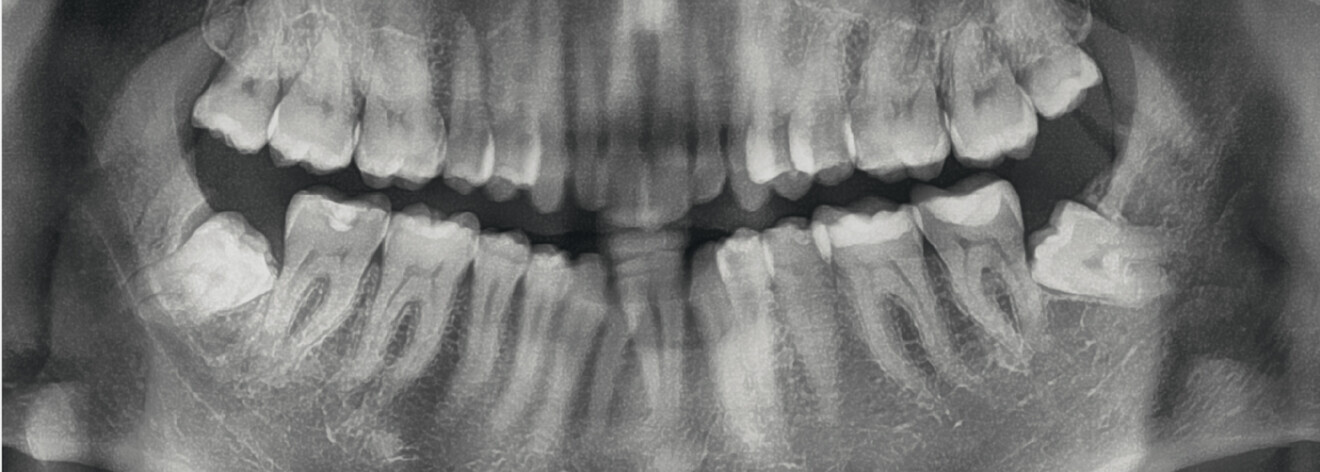

From the periodontal point of view, the patient showed a good attitude to oral hygiene, but crowding of the mandibular incisors made cleaning difficult in that area, causing plaque accumulation and localised gingival inflammation. The panoramic radiograph revealed the presence of the mandibular third molars and confirmed the absence of the mandibular right central incisor (Fig. 10).

Fig. 10: Pretreatment panoramic radiograph.